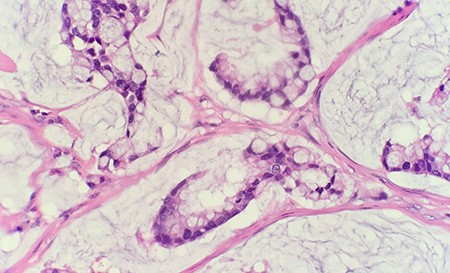

Microscopic examination of the excised mass revealed skin infiltrated by a neoplasm with extensive extracellular mucin pools. Within the mucin pools, there were clusters and strips of malignant intestinal type epithelium. These morphologic features were diagnostic of a moderately differentiated mucinous adenocarcinoma (Fig. 1). The immunohistochemical stains showed that tumor cells were positive for CK7, CK20 and CDX2 while negative for CK5/6 and PAX8, supporting an intestinal phenotype (Fig. 2).

The immunohistochemical stain shows that tumor cells are positive for CDX2 (IHC 20 × ).